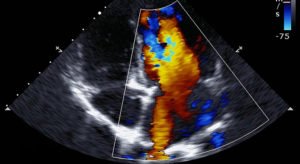

- Show how well blood flows through your heart’s chambers and valves

This two-dimensional technique is used to “see” the actual motion of the heart structures. A 2-D echo view appears cone-shaped on the monitor, and the real-time motion of the heart’s structures can be observed. This enables the doctor to see the various heart structures at work and evaluate them.